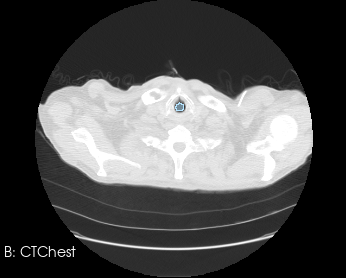

In many cases, the computational domain is derived from patient-specific anatomy. It starts with a medical image: MRI, CT, OCT, IVUS, etc. This provides a 3D volume from which a specific anatomy must be segmented. The segmentation, also known as a label map, is essentially a subset of voxels that are considered part of the anatomy. It is a volumetric mask that represents the object to be modeled (a heart, a vessel, an airway, etc.).

Before generating a 3D volume mesh for CFD, the segmentation undergoes preprocessing for refinement including ensuring a watertight mesh can be generated for simulation and face/surface labeling. The algorithms for doing this are often anatomy dependent, and the identification of faces for boundary conditions often relies on custom scripts. When dealing with many medical images, both manual segmentation and custom scripting can quickly become expensive and time consuming.

3D Slicer is an open-source platform for medical image analysis. It is powerful, flexible, and highly customizable. Slicer provides extensive tools for medical image segmentation as well as a rich ecosystem for processing and cleaning segmentations. A common workflow is to use Slicer for segmentation and surface mesh generation, and then move to other tools for volumetric mesh generation, boundary condition specification, assignment of fluid properties, and other simulation setup. There are also options to generate volumetric meshes within Slicer itself, such as using the SegmentMesher extension or the Vascular Modeling Toolkit (VMTK).